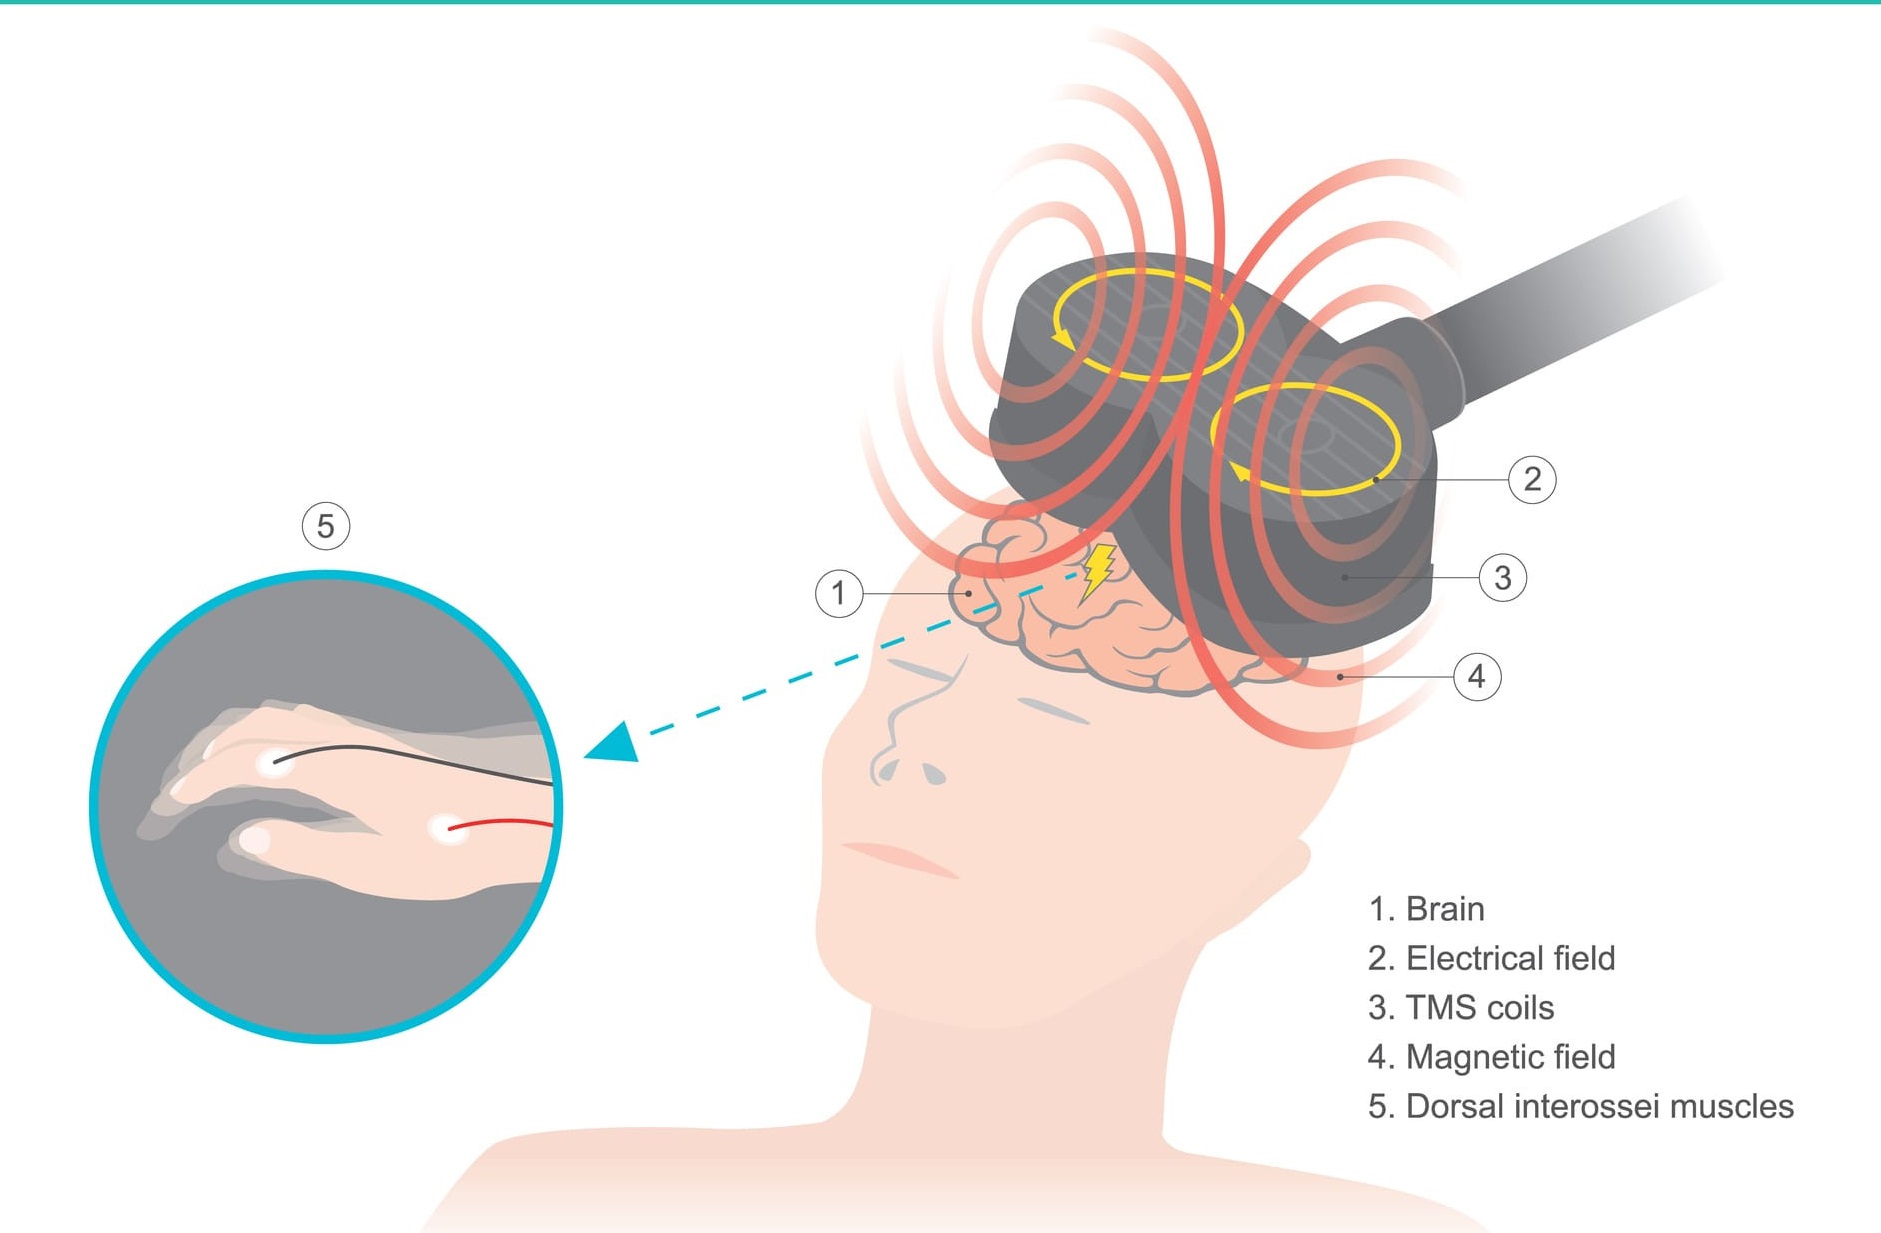

Phương pháp mới cho người mắc bệnh lý thần kinh

Hiện nay, các vấn đề bệnh lý về thần kinh trở nên phổ biến, nhiều người thường xuyên mắc các vấn đề như: xuất hiện những cơn đau đầu không thể giảm đau bằng thuốc; cảm giác đau mỏi vai gáy, đau mỏi vùng thắt lưng nhiều ngày, nhiều tháng; trằn trọc, thức trắng nhiều đêm và không chợp mắt nổi dù đã thử nhiều loại thuốc khác nhau;… Có thể phương pháp điều trị mới dưới đây sẽ là giải pháp cho bệnh nhân mắc các bệnh lý thần kinh.